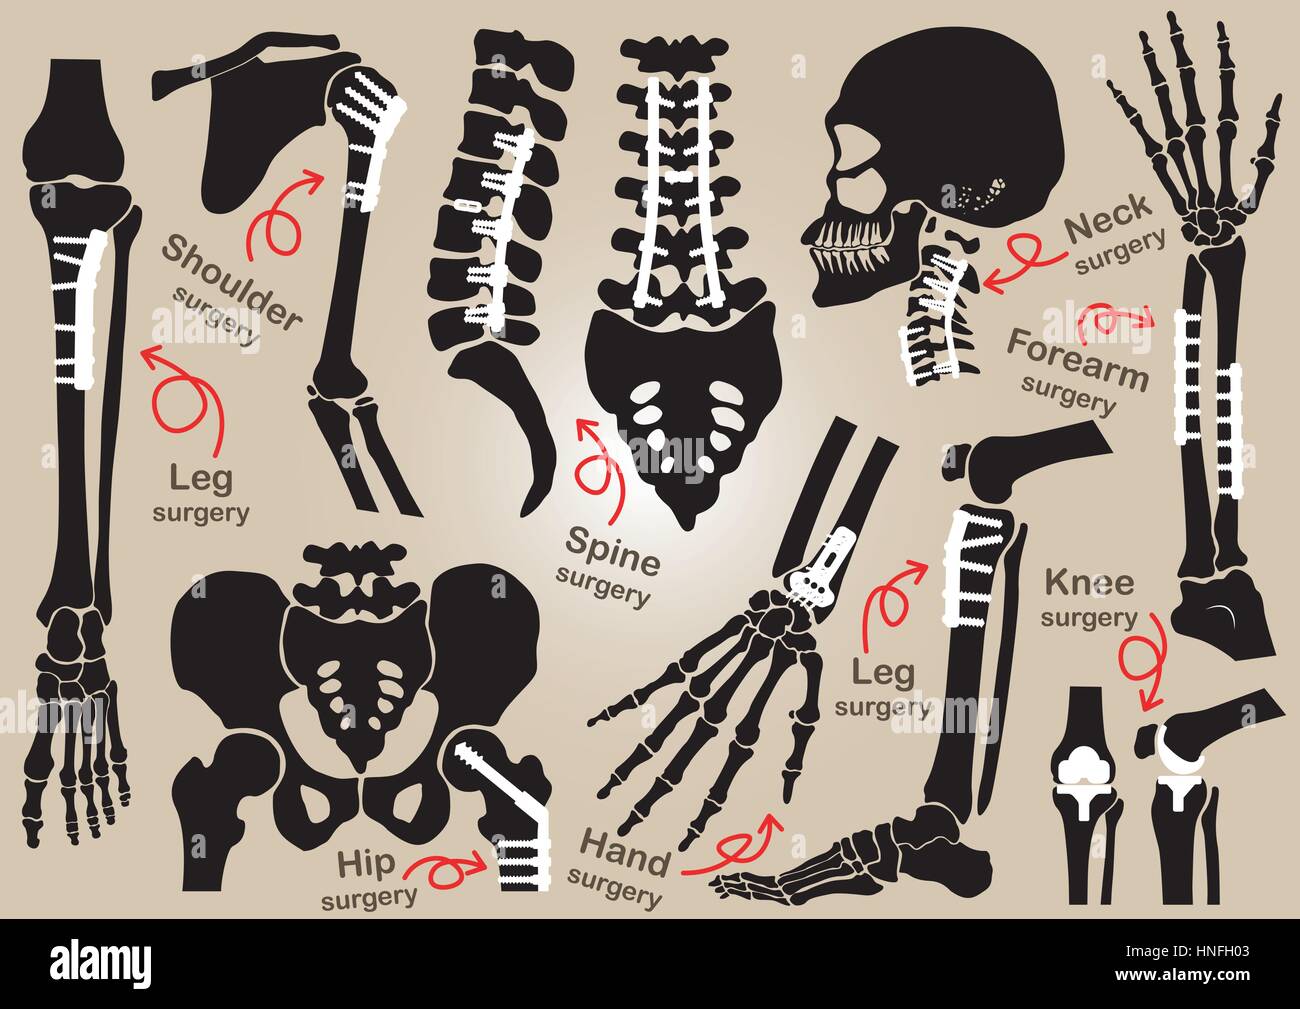

Collection de chirurgie orthopédique ( la fixation interne par plaque et vis )( crâne , tête , cou , colonne vertébrale sacrum , bras , , , main , l'avant-bras Coude ,devrait Illustration de Vecteurhttps://www.alamyimages.fr/image-license-details/?v=1https://www.alamyimages.fr/photo-image-collection-de-chirurgie-orthopedique-la-fixation-interne-par-plaque-et-vis-crane-tete-cou-colonne-vertebrale-sacrum-bras-main-l-avant-bras-coude-devrait-133722963.html

Collection de chirurgie orthopédique ( la fixation interne par plaque et vis )( crâne , tête , cou , colonne vertébrale sacrum , bras , , , main , l'avant-bras Coude ,devrait Illustration de Vecteurhttps://www.alamyimages.fr/image-license-details/?v=1https://www.alamyimages.fr/photo-image-collection-de-chirurgie-orthopedique-la-fixation-interne-par-plaque-et-vis-crane-tete-cou-colonne-vertebrale-sacrum-bras-main-l-avant-bras-coude-devrait-133722963.htmlRFHNFH03–Collection de chirurgie orthopédique ( la fixation interne par plaque et vis )( crâne , tête , cou , colonne vertébrale sacrum , bras , , , main , l'avant-bras Coude ,devrait